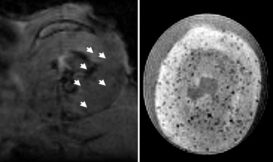

許多患者在腫瘤切除後,因為藥物控制失效,癌細胞的殘兵敗將在移轉到身體其他部位之後又東山再起。現在有了植入型長效藥物釋控技術,在手術之後就能讓腫瘤藥物在患部「長期駐守」,持續控制癌細胞,降低癌症復發的機會。

對於現在的分子醫學研究人員來說,如果能夠追蹤特定種類的細胞在人體內活動的位置-就像你遊山玩水還不忘「打卡」一樣,將會給醫學研究與治療帶來許多很有用的資訊。所以,開發出在能人體中使用的醫療級分子顯影產品,是目前許多醫學研究人員正在努力追尋的聖杯。